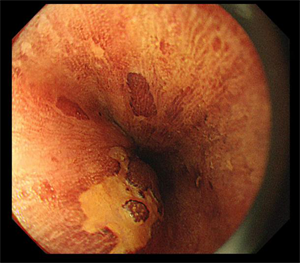

5月14日,80岁的李大爷(化名)因“再发胸闷气喘加重10天”在我院心内科住院期间,经检查,胃镜显示该患者为食管距门齿25~35cm可见两处1.5*2.0cm发红不规则糜烂,病理活检显示为鳞状上皮呈高级别上皮内瘤变(高级别上皮内瘤变相当于原位癌,也称之为食管早癌)。由于该患者曾多次因”慢阻肺、心脏瓣膜病、心功能不全、慢性房颤”住院治疗,且已有80岁高龄,若进行食管癌手术切除治疗风险大、预后生活质量会明显下降。消化内科吴斌及团队根据老人的实际情况反复研究,决定为李大爷行食管早癌消化内镜下黏膜剥离术。

是通过内镜前端针对粘膜、病灶周围进行注射,在胃镜下对病变粘膜进行切割剥离,通过剥离使病灶离开胃壁或者是粘膜层。ESD术具有创伤小、不改变消化道结构、避免外科手术风险、提高术后生活质量等优点,可以帮助早期肿瘤病人达到治愈的目的。